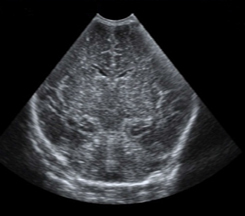

Neonatology Homogeneous Brain 2 Image